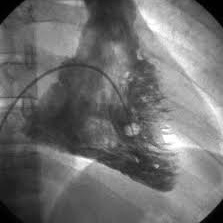

Ventriculografia en reposo. 920404 Idime (2024)

IDIME. Instituto de Diagnóstico Médico. Código de Convenio : 8915

BOGOTÁ

Sede calle 77: Calle 77 No. 23 -35

Sede Occidente: Av. de la Américas No. 69 C 94

INCLUYE UNIDOSIS TECNECIO, Y PIROFOSFATO ESTAÑOSO